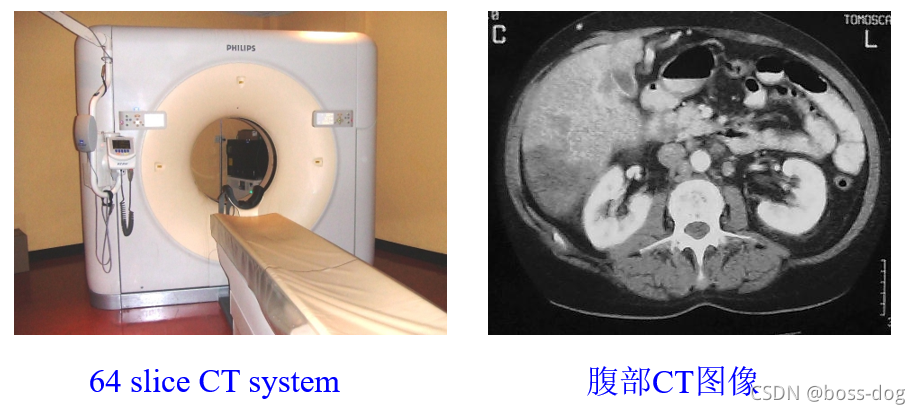

Computed Tomography(CT成像)

A: Sagittal;(矢状位)

B: Coronal;(冠状位)

C: Axial;(轴向的)

D: CT angiography of the head;(头部CT成像,通过静脉注射碘对比剂吸收X光)

E: Blood volume;(头部供血状况)

F: Pseudocolored 3D organ segmentation(三维的器官分割,用来进行体积或距离的测量)